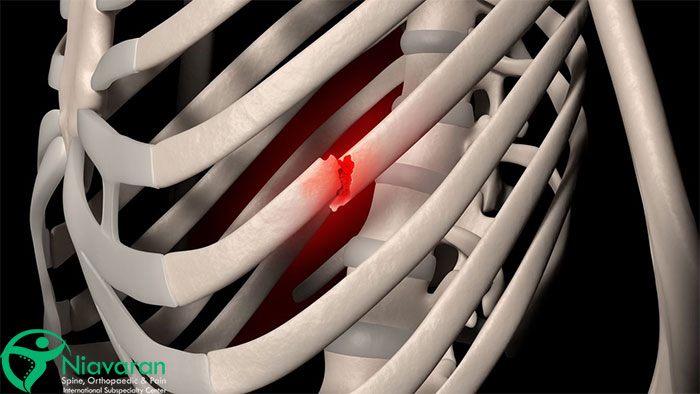

این نوع شکستگی، همانند شکستن یک شاخه خشک درخت به صورت مستقیم، در اثر نیرویی عمودی بر استخوان رخ میدهد. تصور کنید در یک تصادف رانندگی، قفسه سینه شما به شدت به فرمان برخورد میکند. این نیروی مستقیم ممکن است منجر به شکستگی عرضی یکی از دندههای شما شود.

شکستگی خردشده (Comminuted Fracture)

این نوع شکستگی شدیدترین نوع شکستگی دنده است که در آن استخوان به چندین قطعه کوچک خرد میشود. شکستگی خردشده معمولاً در اثر حوادثی با انرژی بالا مانند تصادفات رانندگی با سرعت بالا یا سقوط از ارتفاع رخ میدهد. تصور کنید یک سنگ بزرگ از ارتفاع به قفسه سینه شما برخورد کند. این نیروی شدید ممکن است باعث خرد شدن دنده شود.

شکستگی جابهجا شده (Displaced Fracture)

در این نوع شکستگی، قطعات شکسته شده دنده از محل اصلی خود جابهجا شده و ممکن است روی هم قرار بگیرند یا از هم فاصله بگیرند. این جابهجایی میتواند به دلیل شدت ضربه یا انقباض عضلات اطراف دنده باشد. جابهجایی قطعات شکسته شده میتواند خطر آسیب به اندامهای داخلی را افزایش دهد.